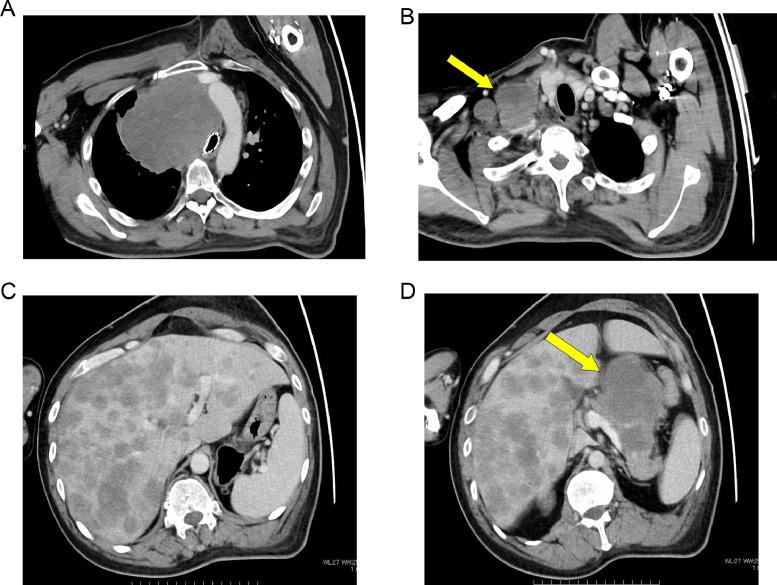

Thoracic -deficient undifferentiated tumor (-UT) is characterized by an undifferentiated rhabdoid morphology and deficiency pathologically. In the 2021 revision of the WHO classification, it was categorized as an epithelial tumor because of its shared genetic background with smoking-related lung cancer. We describe the case of a 44-year-old man with a rapidly enlarging mediastinal mass observed on chest radiography and CT. The tumor was resistant to radiation therapy, chemotherapy, and immune checkpoint inhibitors, and the patient's survival time was approximately 5 months. Familiarity with the clinical background and imaging findings of thoracic -UT is crucial for early diagnosis and treatment planning.

胸段发育不全未分化肿瘤(-UT)的特征是具有未分化的横纹肌样形态且病理表现为发育不全。在世界卫生组织(WHO)2021年的分类修订版中,因其与吸烟相关肺癌具有共同的遗传背景,它被归类为上皮性肿瘤。我们描述了一名44岁男性的病例,胸部X线和CT检查发现其纵隔肿块迅速增大。该肿瘤对放射治疗、化疗和免疫检查点抑制剂均耐药,患者生存时间约为5个月。熟悉胸段-UT的临床背景和影像学表现对于早期诊断和治疗规划至关重要。